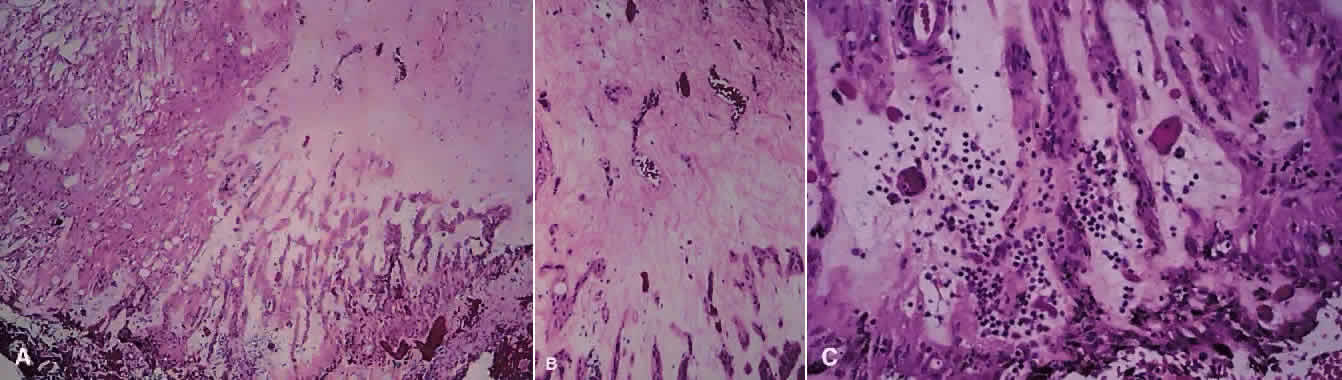

TOXOPLASMOSIS RETINOCHOROIDITIS. Toxoplasmosis accounts for 1% to 5% of AIDS-related retinal infections and usually is acquired as opposed to being congenital.110 Toxoplasmosis in the immunocompromised host differs in its clinical manifestations to that of the immunocompetent host. There tends to be less intraocular inflammation, lack of a preexisting pigmented chorioretinal lesion, and larger, more hemorrhagic areas of involvement, which may be bilateral.110–112 Histopathologic analysis of cases of toxoplasmosis in patients with AIDS shows the presence of Toxoplasma cysts, necrosis of the retina, and a minimal lymphocytic infiltrate within all layers of the retina (Fig. 13).110 In addition, the choroid shows the presence of histiocytes, plasma cells, and eosinophils.113

Fig. 13 A. Right fundus from patient with the acquired immunodeficiency syndrome showing a large area of necrotizing retinitis (pigmentation within area of necrosis, possibly representing previous site of activity) with hemorrhage, which, on histopathologic analysis (B and C), revealed retinal necrosis and the presence of cysts consistent with Toxoplasma gondii (hematoxylin and eosin; B × 200, C × 500). D. Electron microscopy shows tachyzoites within cysts.